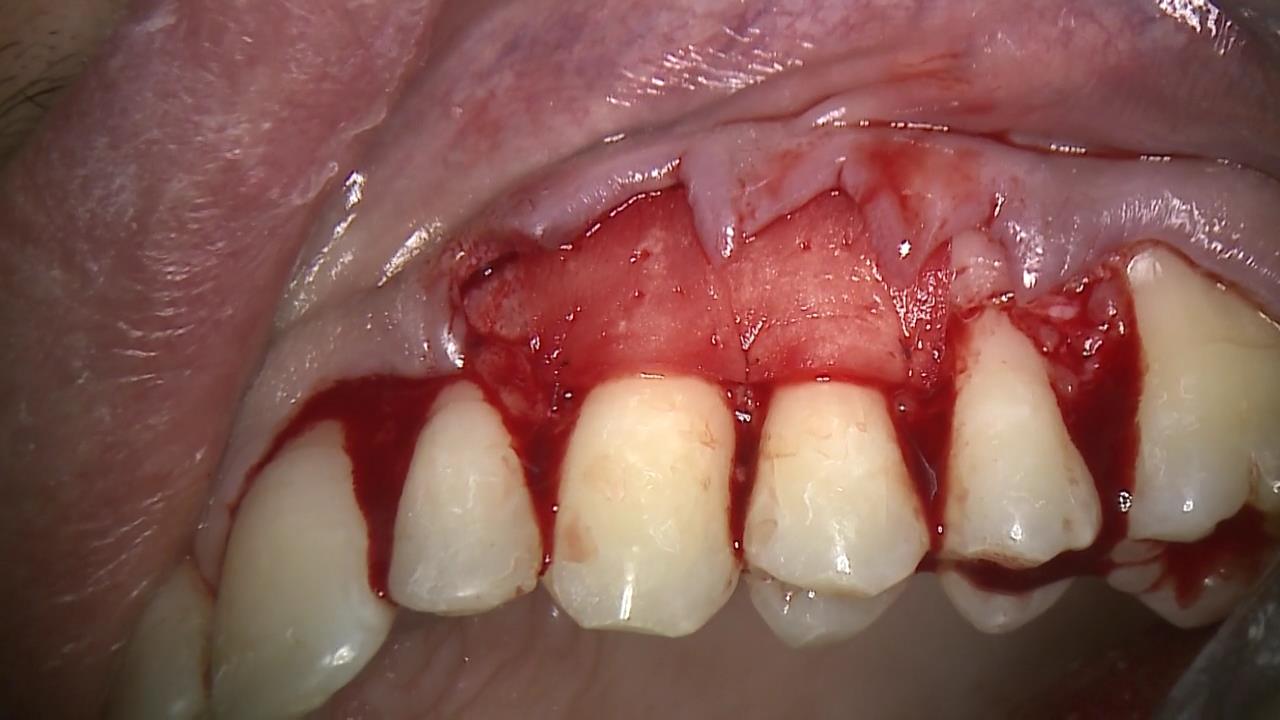

2/12 - Flap design: coronally advanced envelope type flap for multiple gingival recessionsMultiple recession coverage with mucoderm® and Straumann® Emdogain® - 4 year follow-up - Prof. G. Zucchelli & Dr. M. Stefanini

3/12 - Flap elevation: with a split-full split approachMultiple recession coverage with mucoderm® and Straumann® Emdogain® - 4 year follow-up - Prof. G. Zucchelli & Dr. M. Stefanini